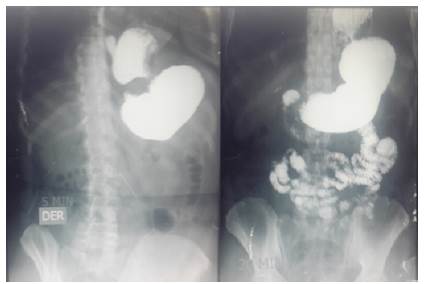

Una radiografía de serie digestiva alta reportó hernia hiatal paraesofágica con disminución del calibre en la parte alta de la cavidad gástrica y paso normal del contraste al intestino delgado y colon (figura 2).